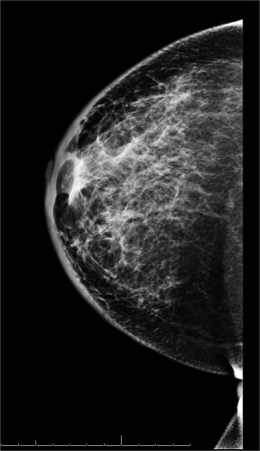

- Biennial (every other year) screening mammography:

- For women aged 50 to 74 years:

- With a category B recommendation.

- USPSTF states that the decision to start screening mammography prior to age 50 years:

- Should be an individual one and should occur biennially if chosen:

- This is a category C recommendation.

- The American College of Radiology and the Society of Breast Imaging recommend:

- Annual screening mammography beginning at age 40 years.

- The American Cancer Society recommends:

- Regular screening mammography for women beginning at age 45 years:

- With qualified recommendations for women aged 45 to 54 years to be screened annually.

- Women 55 years and older:

- To transition to biennial screening or have the option to continue annual screening.

- For women aged 40 to 44 years to have the option to begin annual screening.

- The American Society of Breast Surgeons recommends:

- That average risk women ages 40 to 44 years discuss the risks and benefits of screening with their physicians.

- Annual mammographic screening is recommended:

- For women ages 45 to 54 years.

- Annual or biennial screening is recommended:

- For women 55 years and older:

- Based on a shared decision-making discussion of risks and benefits.

- Biennial screening is recommended for women age 75 years and older if estimated life expectancy is at least 10 years.